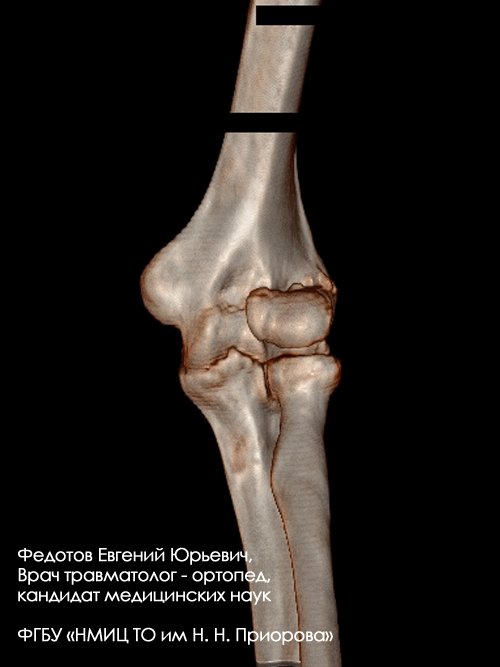

Закрытый внутрисуставной перелом головочки, блока мыщелка и наружного надмыщелка плечевой кости со смещением.

Операция: открытая репозиция отломков дистального мыщелка плечевой кости, наружного надмыщелка, остеосинтез пластиной и винтами.

Закрытый внутрисуставной перелом головочки и части блока плечевой кости со смещением.

Операция: открытая репозиция отломков головочки и части блока плечевой кости, остеосинтез винтами.